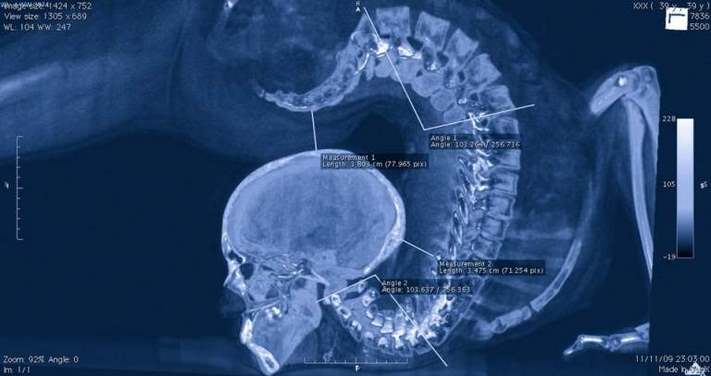

Ակրոբատի ողնաշարը հնարք կատարելիս